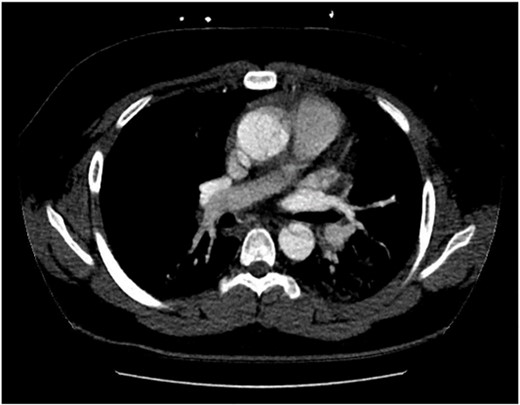

The patient was hemodynamically stable during his admission; however, worsening pain profile led to a serial electrocardiogram showing sinus rhythm with ST segment changes consistent with ischemia. There was an initial troponin rise of 245 ng/L progressing to a peak of 922 ng/L. The remaining blood panel was unremarkable. Chest X-ray showed no widened mediastinum and clear lung fields. A bedside transthoracic echocardiogram demonstrated a dissection flap with severe aortic regurgitation in the ascending aorta. Computed tomography aortogram was consistent with a Stanford Type A aortic dissection extending from the aortic root to the bifurcation of the common iliac arteries (Figs 1 and 2). There was involvement of the right brachiocephalic artery and right common iliac.

Computed tomography aortogram Axial Image of Stanford Type-A Aortic Dissection extending into arch and descending thoracic aorta.